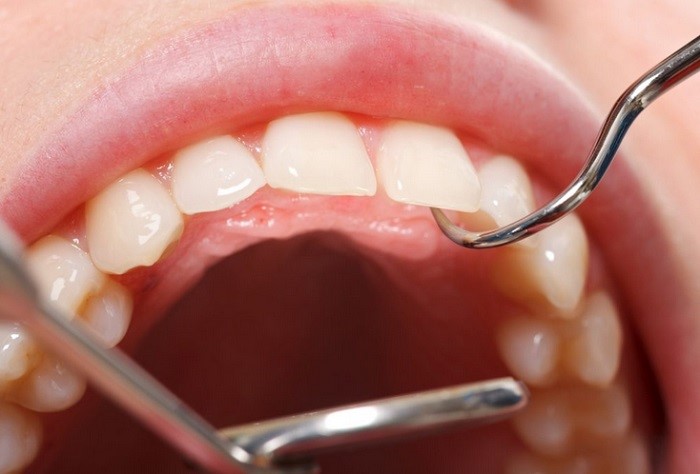

Форма папилломы – всегда округлая, от 0,2 до 2 см, а поверхность может быть складчатой, бородавчатой или мелкозернистой. Внешних изменений слизистой оболочки вокруг разрастания не наблюдается. Болевой синдром отсутствует. Основание (ножка) бывает как узким, так и широким.

Папилломатоз (множественные папилломы) чаще выявляется на небе. После случайного прикусывания новообразование начинает кровоточить, а позже приобретает темный цвет вследствие кровоизлияния в его полость.

Кожные покровы пациента в проекции папилломы – без изменений, а открывание рта – свободное.